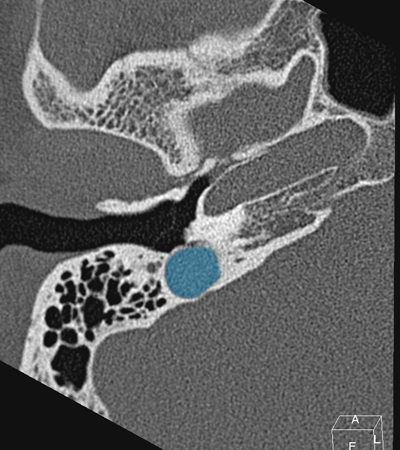

Horizontal petrous carotid Jugula bulb Sigmoid sinus Anterious wall of bony EAC (tympanic bone) Eustachian tube Tympanic membrane Facial nerve (f3), mastoid segment

Radioanatomy of Temporal bone